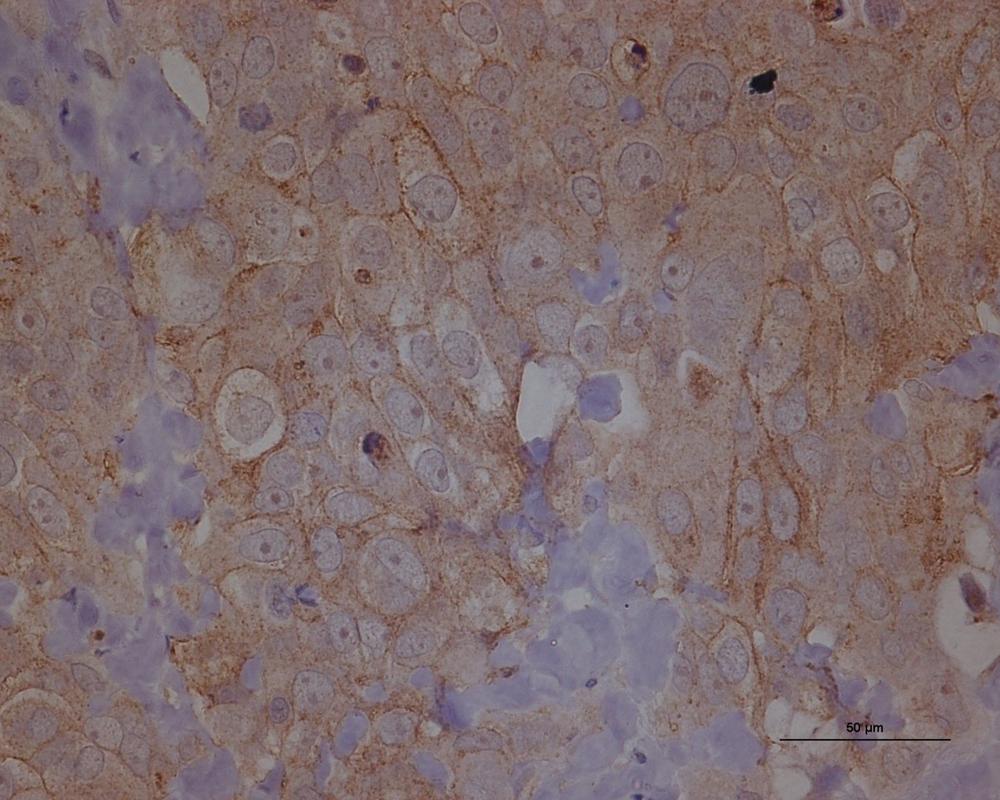

El segundo estudio, publicado en la revista científica ‘Journal of Experimental & Clinical Cancer Research’, ofrece a los investigadores una comprensión más profunda de cómo los tumores de ovario desarrollan resistencia a la quimioterapia, lo que ocurre en alrededor del 80 por ciento de las pacientes con cáncer de ovario seroso de alto grado y, en última instancia, las lleva a sucumbir a la enfermedad.

Sin embargo, mediante la secuenciación del genoma completo, descubrieron por primera vez que no es así. Por el contrario, parece más probable que la mayoría de los tumores serosos de ovario de alto grado tengan la capacidad de sobrevivir a la quimioterapia desde una fase muy temprana, dijo Jones, que también es la coautora de este estudio.